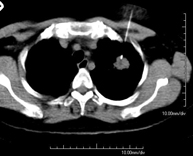

- Thorax

- Chest CT

Diagnostic test that provides high definition anatomical images of the chest (lungs, heart, mediastinum, great vessels, rib cage, etc.) using CT (Computed Tomography) equipment. These images are then examined on a workstation that allows bidimensional reconstructions in different planes of space and also 3D reconstructions (volumetric). Some studies require the use of an iodinated contrast agent to improve image definition.